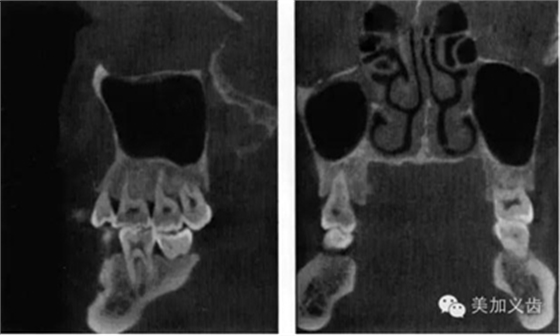

——錐形束CT

這個是三維放射線重建影像可以全面、準確的評價解剖學結(jié)構(gòu),包括可用骨形態(tài)的三維數(shù)值,通俗點講就是可以看到可用骨的垂直向、近遠中向和頰舌向的數(shù)值。

其優(yōu)點是:可以提供精確的、亞毫米級測量數(shù)值,與印模結(jié)合,通過CBCT數(shù)據(jù)來實現(xiàn)模擬手術并制作外科導板。CBCT的放射量與傳統(tǒng)CT相比要小很多,放射時間短,操作也比較簡單。

其缺點是:設備成本還是比較高,分辨率略顯不足,而且會存在一定程度上的影像學偽影。